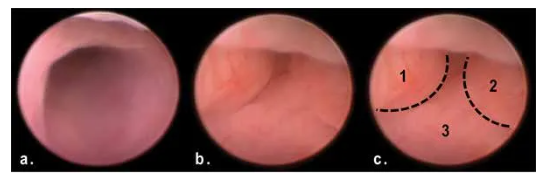

2. AOM/DSS造模50天后,與正常結(jié)腸(a)相比,模型組產(chǎn)生了多發(fā)性息肉樣腫塊阻塞末端結(jié)腸管腔(b、c)。